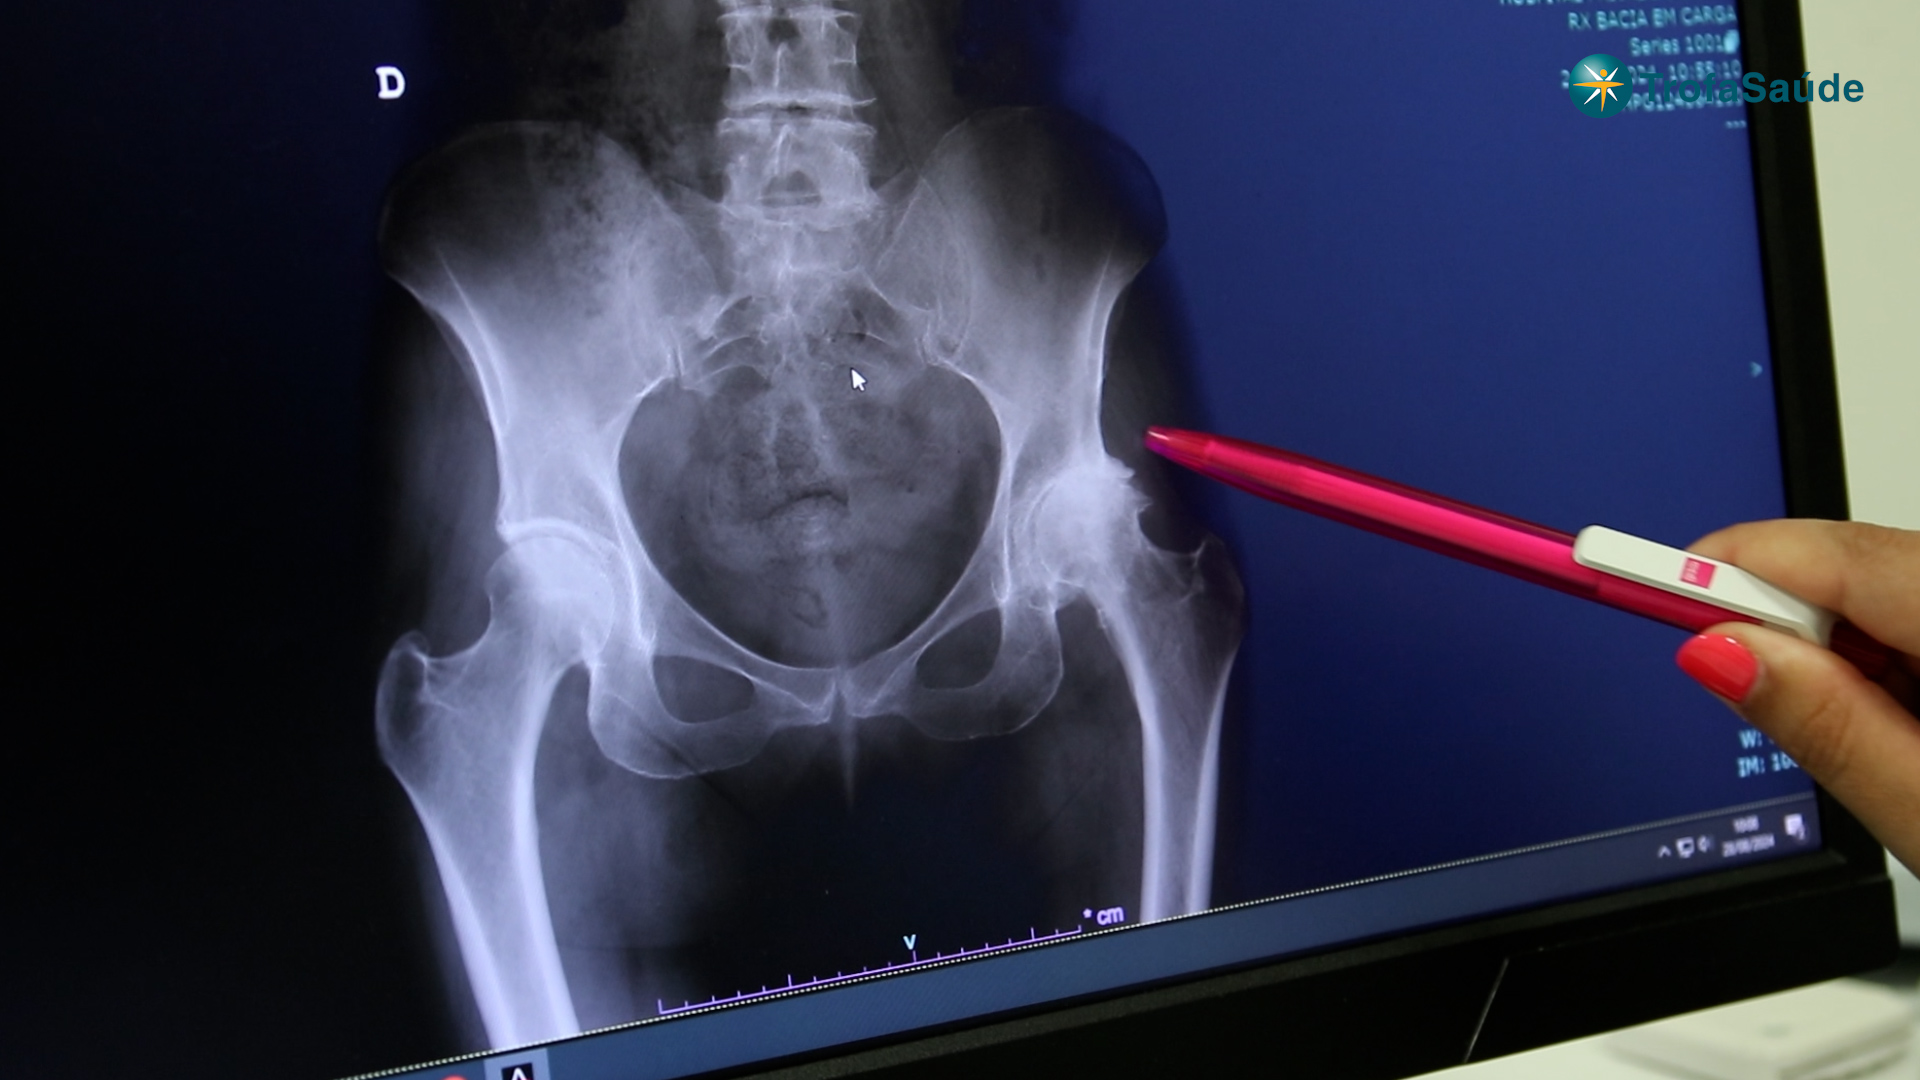

O diagnóstico baseia-se na avaliação clínica e em exames de imagem.

Radiografia da anca (principal exame)